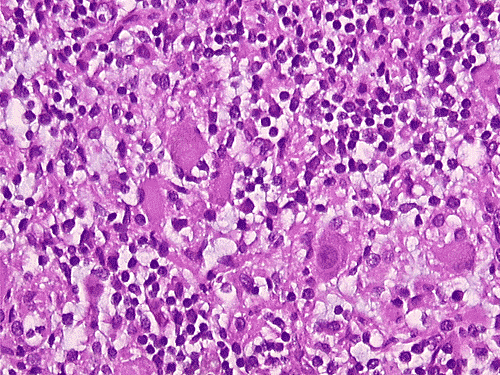

The overall tissue preservation is less than optimal because of postmortem autolysis. Panel A and B are taken from the cerebellum. The molecular layer, Purkinje cell layer, and internal granular layer are included (Panel A). Solitary eosinophilic intracytoplasmic inclusions of variable size are present in the Purkinje cells. No inflammatory cell infiltration is present in the cerebellum. The vacuolar spaces (Panel B) is partly due to autolysis and partly due to hypoxic/ischemic changes. Pyramidal cells in the hippocampus (Panel C), cortical neurons in parietal lobe (Panel D) and other neocortical areas adopted an elongated and contracted contour with loss of nuclear details. These are histologic features consistent with hypoxic/ischemic changes. Similar to the cerebellum, solitary eosinophilic cytoplasmic inclusion bodies are present and there is no inflammatory cell infiltration. Multiple eosinophilic cytoplasmic inclusion bodies within a single neuron are occasionally found. Some of these neurons containing multiple inclusions from the substantia nigra are illustrated in Panel E. Although inflammatory cell infiltration is scant in the cerebrum and cerebellum, perivascular chronic inflammatory cell infiltrations are common in the medulla (Panel F and G), in the paravertebral sympathetic ganglion (Panel H and I) and in the spinal cord (not shown). Intracytoplasmic inclusions, however, are not found in the medulla, spinal cord, and paravertebral sympathetic ganglion. Under the electron microscope, rod-shape or bullet-shaped viral particles are found (Panel J).

The brain and spinal cord may appear swollen but are usually free of focal lesions. Histopathologically, rabies is a widespread polioencephalomyelitis. Leptomeningeal and parenchymal perivascular lymphocytic infiltrations are usually present but often not intense. Neuronophagia can also be seen. The amount of inflammation of the case under discussion is, in fact, on the intense side of the scale. The pathognomonic Negri bodies 10, 11, 12 are sharply delineated, round to oval, eosinophilic, neuronal cytoplasmic inclusions; first described by Negri in 1903 10. These inclusions are often solitary but may also be multiple in a single neuron. Lyssa bodies refer to less well delineated and more pleomorphic neuronal cytoplasmic viral inclusions. Babes’ nodules refer to clusters of microglia that remain after destruction of neurons. When immunohistochemistry is employed, the distributions of viral antigen are far more extensive than that estimated by conventional light microscopy 13. Negri body and rabies viral antigen as demonstrated by immunohistochemistry are most commonly seen in large neurons of the hippocampus (Pyramidal cells), cerebellum (Purkinje cells), thalamus, basal ganglia, cerebral cortex and in the brain stem, especially gray matter of the pons and medulla. They are also found in spinal cord motor neurons and dorsal root ganglion, especially in the paralytic form.  Immunohistochemistry also demonstrated rabies viral antigen in astrocytes and oligodendrocytes 13. Characteristically, a striking discrepancy between the degree of inflammation and amount of inclusion bodies is observed, as in our case, in many cases.